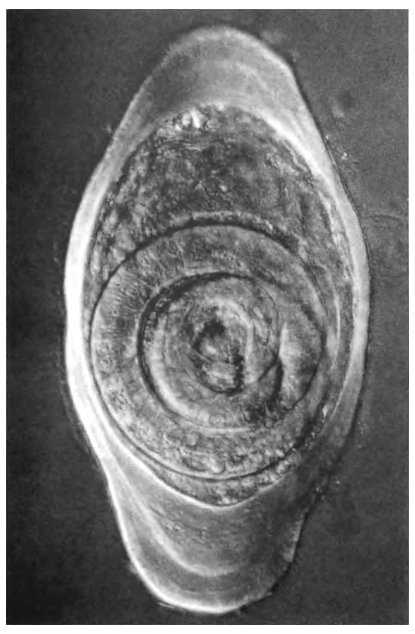

![]() Анкилостому носит в себе 1,3 млрд человек. При помощи своих мощных зубов эти паразиты рассекают стенку кишечника (врезка) и пьют кровь из раны. ![]() Ленточные черви, достигающие в длину более 15 м, являются самыми крупными паразитами человека. ![]() Известно пять тысяч видов ленточных червей, живущих в самых разных животных, и, вероятно, многие тысячи из них еще ждут своего открытия. Головки особей каждого вида специально приспособлены для закрепления в теле хозяина. ![]() Шистосомой (известна как кровяной сосальщик) заражены более 200 млн человек. Слева вверху: молодые паразиты вылупляются из яиц в пресной воде и ищут нового хозяина — улитку. Справа вверху: внутри улитки паразиты проживают несколько поколений, прежде чем превращаются в ракетообразные существа, известные как церкарии. Внизу: церкарии проникают в организм человека сквозь кожу, достигают зрелости и окончательно поселяются в венах хозяина. ![]() Trichinella, вызывающая трихинеллез, является исключительным паразитом: это животное с образом жизни вируса. Ее личинки проникают в отдельные мышечные клетки и, сворачиваясь внутри в клубок, берут под контроль мышечную ДНК, что помогает им сделать клетку более удобным жилищем. ![]() Вверху: одноклеточный паразит Plasmodium falciparum, вызывающий малярию. На фото — новое поколение паразитов выходит из эритроцита. Слева внизу: еще один одноклеточный паразит — Trypanosoma brucei, вызывающий сонную болезнь. Справа внизу: Toxoplasma gondii (показанная здесь внутри клетки хозяина) является одним из наиболее успешных паразитов на Землей в некоторых районах мира ею инфицировано 90 % населения. ![]() Паразиты часто выбирают строго определенные — и весьма странные — места для жизни. Эти ракообразные устраиваются во рту рыбы, съедают ее язык и занимают его место. После этого они начинают выполнять функции языка: рыба может с их помощью хватать и глотать добычу. ![]() Еще один замечательный паразит — Ommatokoita elongata — живет только в гренландских акулах, которые путешествуют под арктическими льдами. Более того, Ommatokoita живет только в их глазах, закрепляясь в стекловидном теле глаза с помощью специально приспособленных ног. ![]() Насекомые — мастера паразитировать на других насекомых. Вверху: паразитические осы откладывают яйца внутрь гусениц, и личинки медленно пожирают своих хозяев живьем, прежде чем выползти наружу и окуклиться. Внизу: насекомое Xertos peckii паразитирует на непаразитической бумажной осе. Когда из яиц выходят личинки, самка остается внутри и поедает половые органы хозяина, а самец пробуривается наружу и летит к другой осе, чтобы найти себе пару. Во взрослом состоянии самец живет всего несколько часов; в результате он развил у себя замечательный орган, помогающий ему быстрее отыскать самку. У самца 100 миниатюрных глаз, каждый из которых имеет собственную радужную оболочку и способен сформировать полное изображение. ![]() Когда паразит полностью использовал своего хозяина, ему необходимо выбраться наружу. Вверху: грибок вырастает из муравья. Внизу: червеобразный паразит, известный как нематоморф, выходит из своего хозяина — сверчка. ![]() Колючеголовые черви, подобно многим другим паразитам, успевают пожить в двух и более хозяевах. Многие из них сначала живут в насекомых и ракообразных, а затем перемещаются в хищников, например в птиц. Чтобы попасть в этих хищников, паразиты делают своих промежуточных хозяев глупыми и беспечными — легкой добычей для хищников. ![]() Вверху: паразитический рачок Sacculina carcini проникает в краба и заполняет все его тело целой сетью «корней». На том месте, где у краба должна находиться специальная сумка для яиц, Sacculina формирует мешочек, полный личинок (среднее фото), и вынуждает краба заботиться не о своем потомстве, а о потомстве паразита. Внизу: улитка тоже может стать жертвой паразита — трематоды Leucochloridium paradoxum. Окончательные хозяева этого паразита — птицы. Чтобы привлечь их внимание, Leucochloridium забирается в прозрачные щупальца улитки. Полосатые трематоды просвечивают сквозь щупальца, напоминая гусениц, и голодные птицы с готовностью хватают зараженных улиток. |